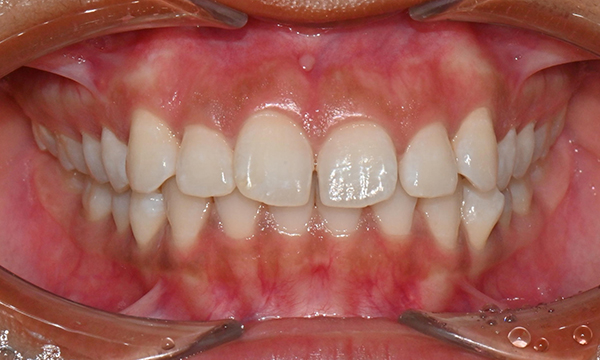

위아래 앞니 사이가 벌어져서 공간이 있었고, 앞니에 약간씩 배열이 틀어진 덧니가 있었습니다. 정면에서 보았을 때 윗니와 아래 앞니가 깊게 물려서 아래 앞니가 잘 보이지 않는 과개교합 양상을 보이고 있었습니다. 또한 왼쪽 아래 작은 어금니가 90도 앞으로 돌아가서 좌측 치아 배열 및 교합이 좋지 않은 상태였습니다.

초진시 구내사진 (2025. 3.31)

교정 마무리 후 사진으로 위아래 치아 배열이 개선되었고 공간이 모두 닫혔습니다. 위아래 앞니가 깊게 물리는 과개교합도 처음에 비하여 많이 개선되었습니다. 다만 아래 작은 어금니 배열로 인하여 왼쪽 어금니 교합은 아직 완벽하지 않은 상태로, 추후 본국으로 돌아가서 자료를 transfer 해드려서 이어서 치료를 받기로 하셨습니다.